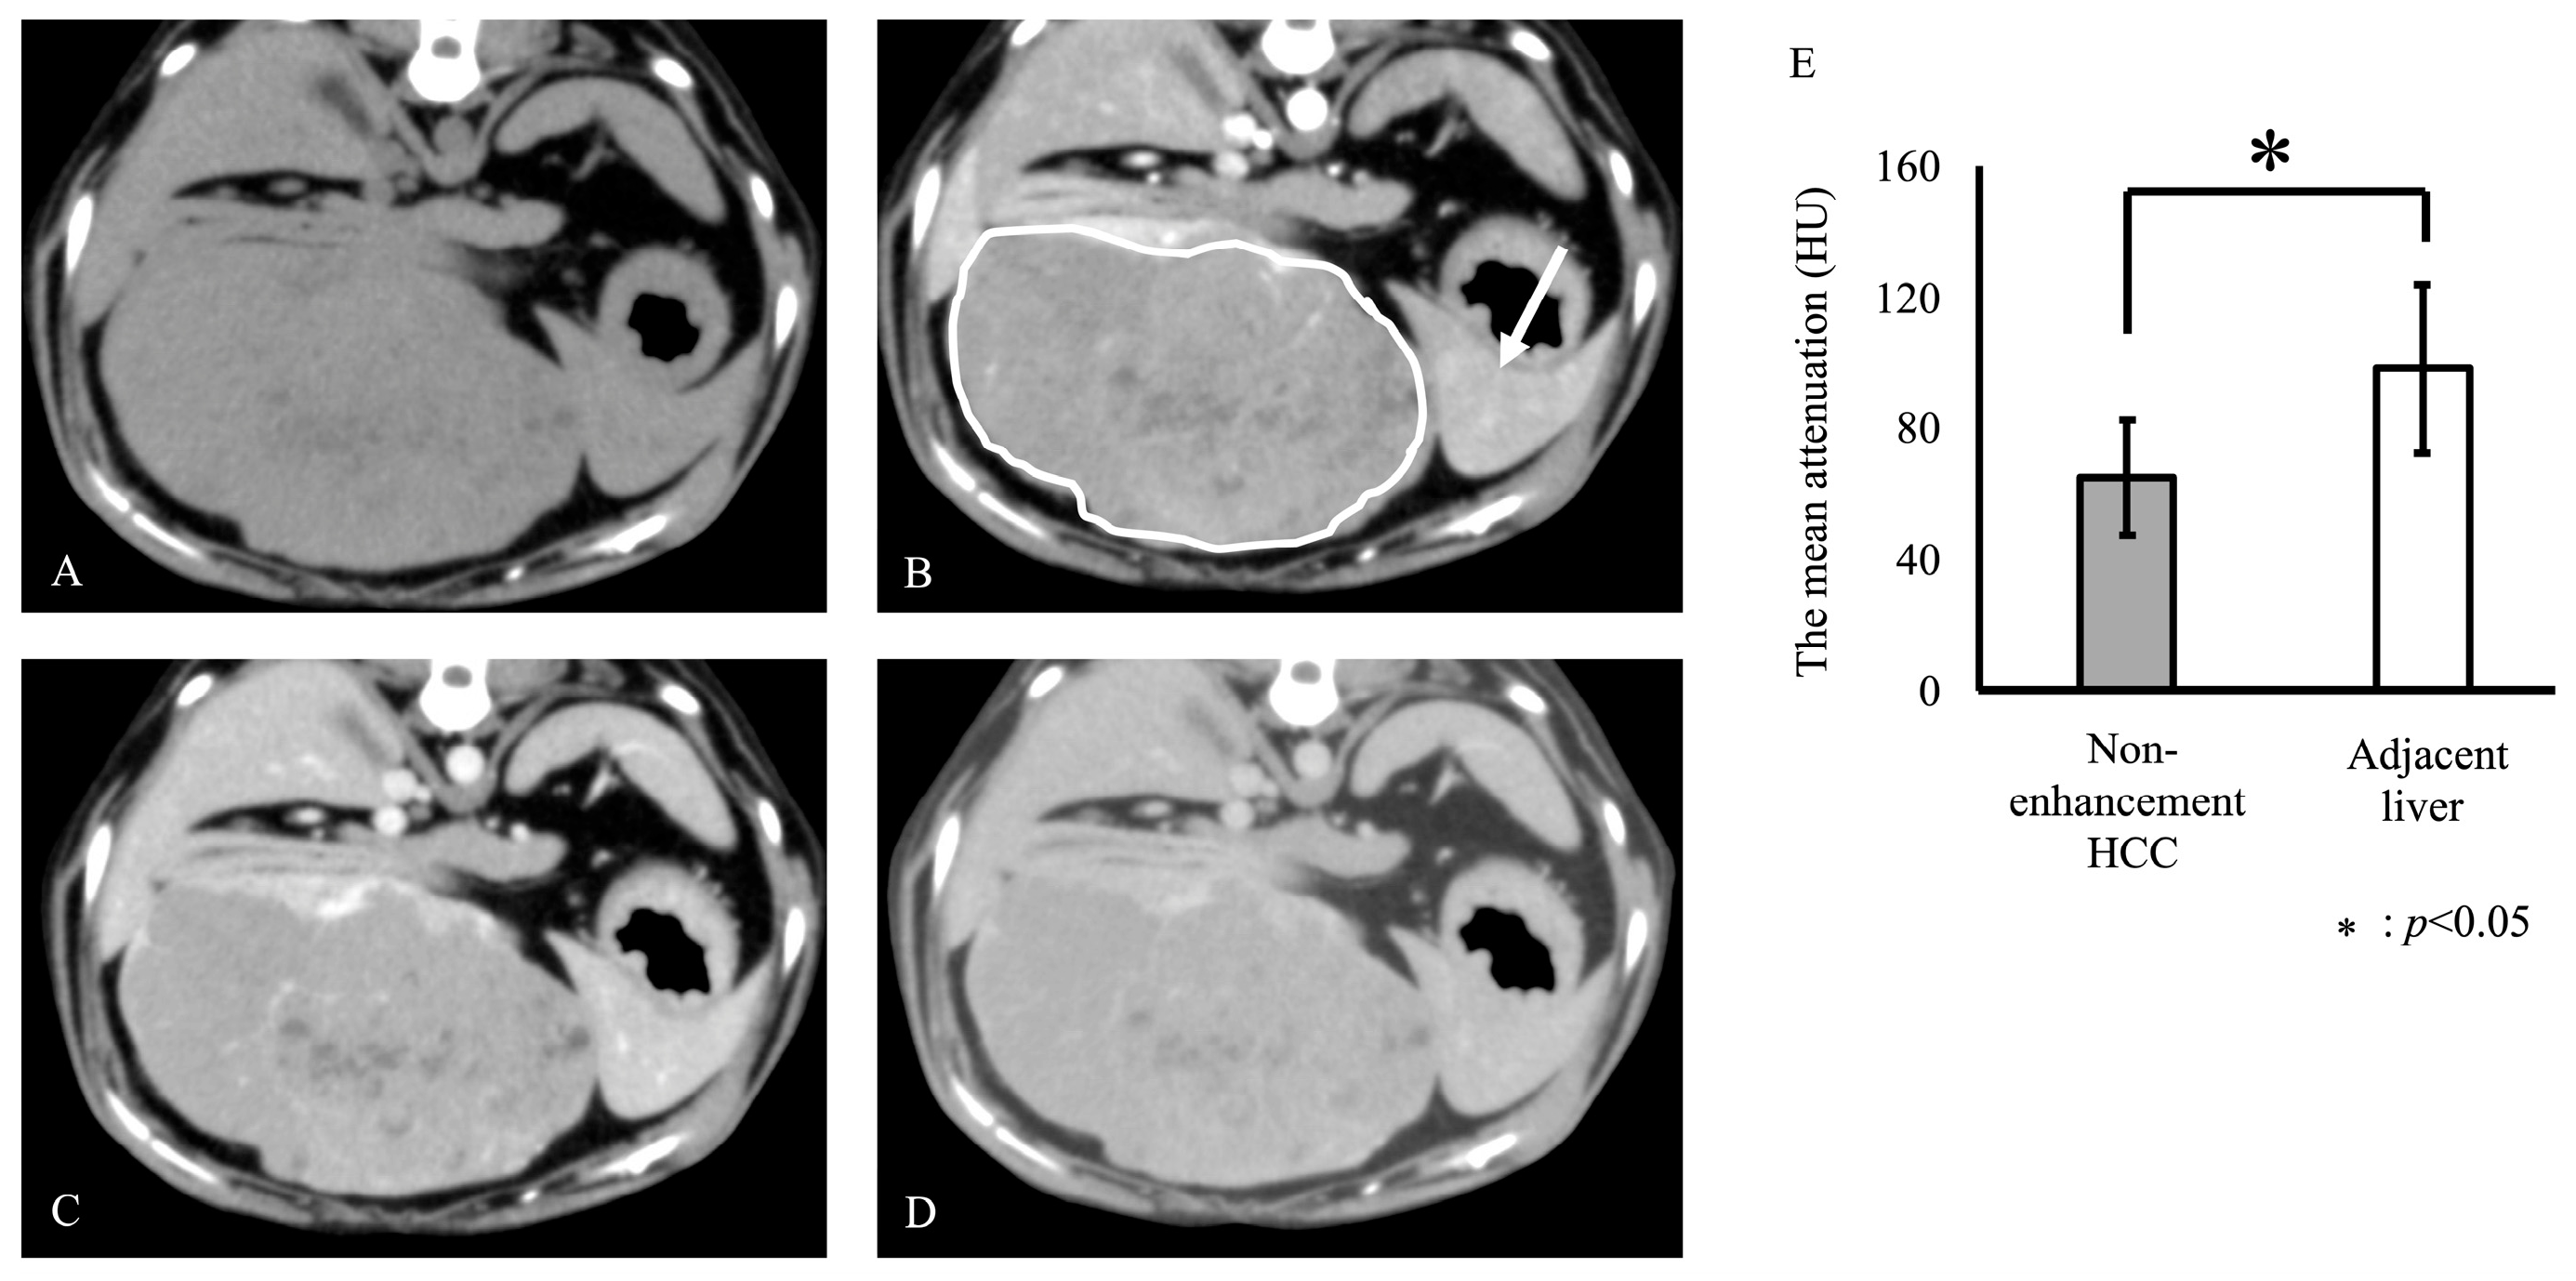

| G3 | non-enhancement | 14.4 | IF | Shiba | - | - |

| G3 | non-enhancement | 12 | IF | Border Collies | - | - |

| G3 | non-enhancement | 9 | SF | Brussels griffon | - | - |

| G3 | non-enhancement | 8 | IM | Shiba | - | - |

| G3 | non-enhancement | 8.6 | IF | Shiba | - | - |